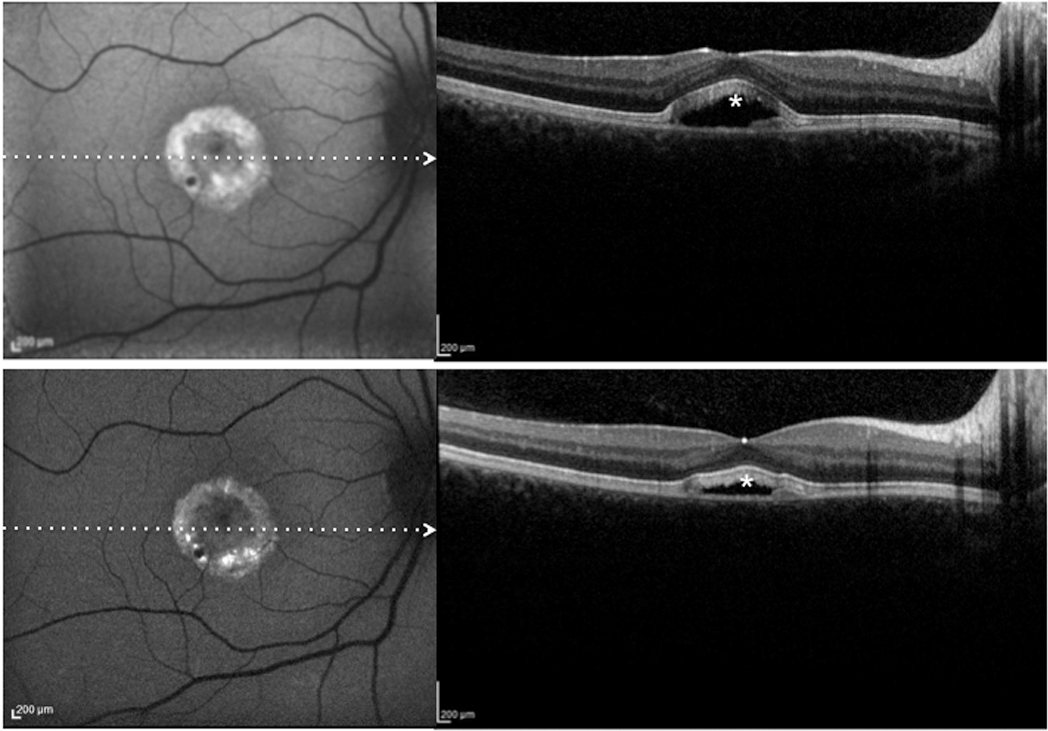

Figure 7. Patient #21.Blue fundus autofluorescence (FAF) and spectral-domain optical coherence tomography (SD-OCT) reveal the right

eye affected with vitelliruptive lesion at both study entry and last follow-up visit (50 months later). Blue FAF frames and

SD-OCT scans at study entry (top left and bottom right panels) show reabsorption of the hyperautofluorescent/hyperreflective

subretinal material (asterisk) and replacement by a fluid component. At the last follow-up visit, blue FAF remained almost

unchanged (top right panel), while SD-OCT showed a decrease in subretinal fluid (asterisk; bottom right panel).